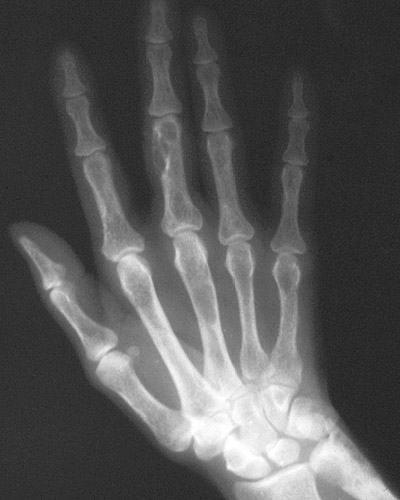

| This radiograph of the hand demonstrates osteitis fibrosa cystica with areas of rarefaction, typical of patients with primary hyperparathyroidism. As seen in the more advanced case here, cystic areas develop from the osteoclastic activity, and the marrow becomes fibrotic. Microfractures can occur in the weakened bone. |